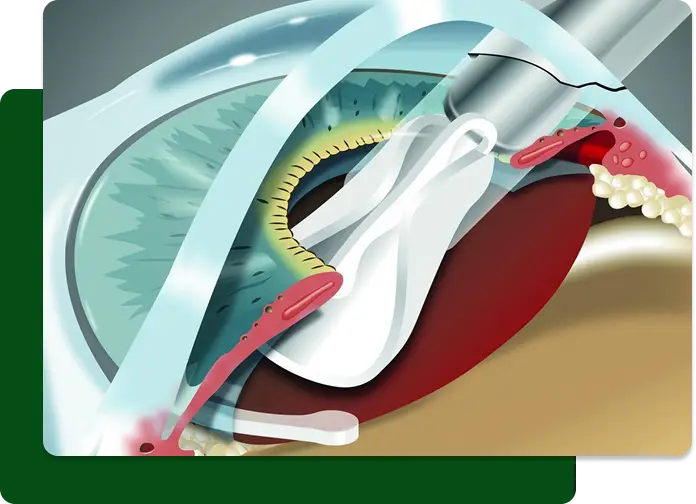

Der refraktive Linsentausch – auch als Clear Lens Exchange (CLE) oder Austauschlinse bekannt – ist eine moderne und sichere Methode, um Fehlsichtigkeiten wie Kurz- und Weitsichtigkeit sowie Alterssichtigkeit dauerhaft zu korrigieren. Dabei wird die körpereigene Linse durch eine individuell angepasste Kunstlinse ersetzt, die optimal auf Ihre Sehbedürfnisse abgestimmt ist. Das Verfahren entspricht der Behandlung des Grauen Stars, der weltweit am häufigsten durchgeführten, ambulanten Behandlung und eignet sich besonders für Patientinnen und Patienten, bei denen Augenlaserverfahren wie LASIK oder ICL nicht infrage kommen – etwa aufgrund von Alterssichtigkeit oder beginnendem Grauen Star.

Die Behandlung erfolgt ambulant und unter örtlicher Betäubung. Nach dem Entfernen der natürlichen Linse wird die neue Kunstlinse in den Kapselsack eingesetzt. Das Sehvermögen verbessert sich meist bereits kurz nach dem Eingriff deutlich. Durch den Linsentausch kann nicht nur die Fehlsichtigkeit korrigiert, sondern auch die spätere Entwicklung eines Grauen Stars verhindert werden. Zudem bleibt die Hornhaut vollständig unberührt – ein großer Vorteil für Menschen mit dünner oder empfindlicher Hornhaut.